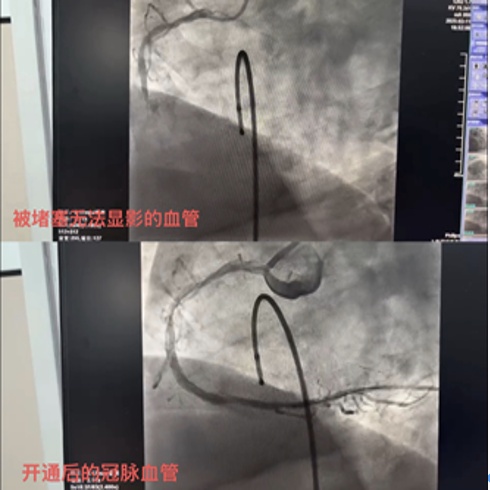

患者回到抢救室后,短短20分钟内反复出现恶性室性心律失常——室速室颤“电风暴”,多次陷入生命边缘。急诊内科与心血管内科团队高效协作,边复苏边实施电击除颤,最终经过6次电击除颤,患者恢复窦性心律,意识转清。随即护送至心导管室。冠状动脉造影检查显示:患者右冠状动脉中段100%闭塞,介入科团队精准操作,顺利开通闭塞血管,恢复心肌供血。术后,患者生命体征平稳,被转入冠心病监护病房(CCU)进一步观察治疗。

堵塞的冠脉通过支架植入开通后